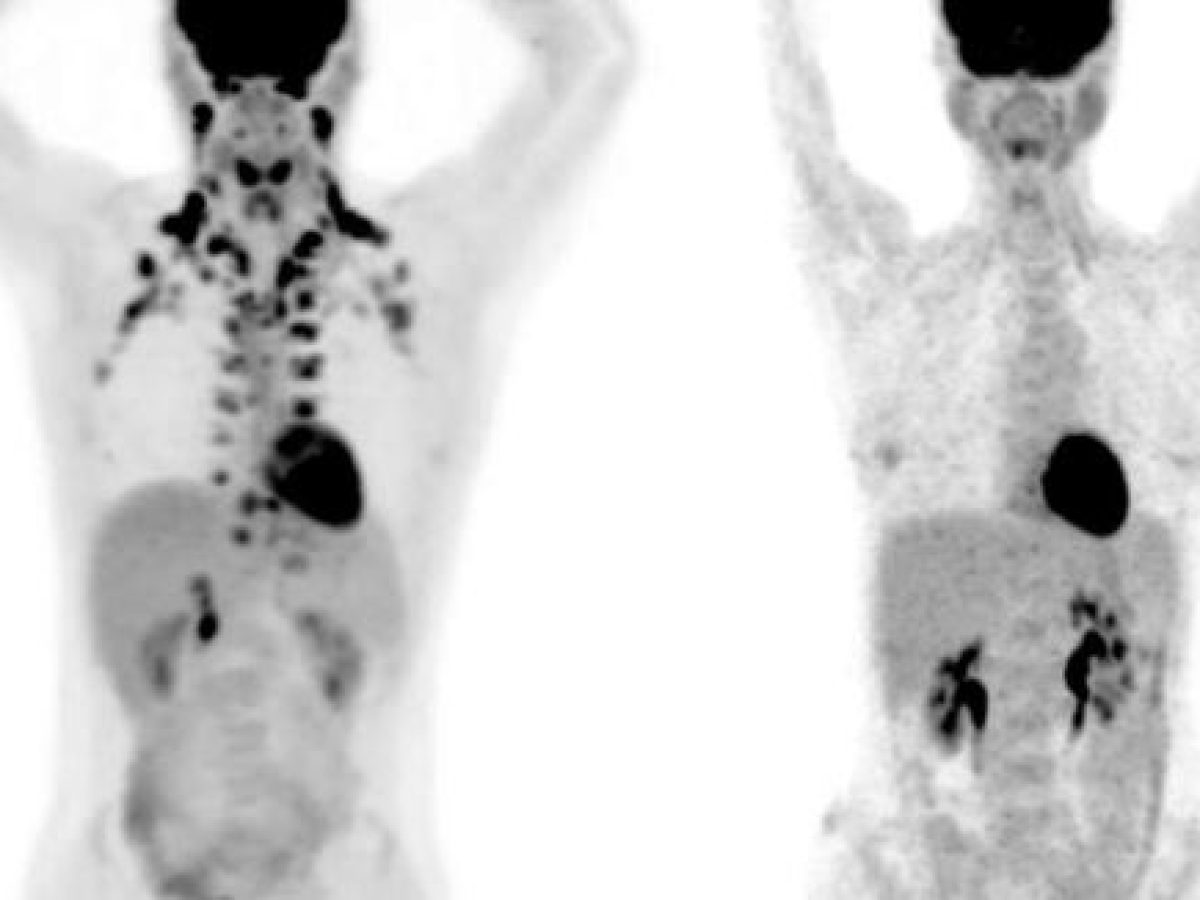

Σε αυτές τις εξετάσεις PET, το άτομο στα αριστερά έχει άφθονο καφέ λίπος γύρω από τον λαιμό και την αυχενική μοίρα της σπονδυλικής στήλης. Το άτομο στα δεξιά δεν έχει ανιχνεύσιμο καφέ λίπος.